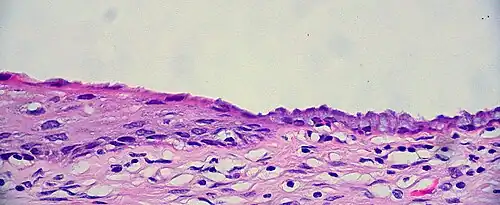

The endocervical mucosa is about 3 mm (0.12 in) thick and lined with a single layer of columnar mucous cells. It contains numerous tubular mucous glands, which empty viscous alkaline mucus into the lumen.[4] In contrast, the ectocervix is covered with nonkeratinized stratified squamous epithelium,[4] which resembles the squamous epithelium lining the vagina.[17]: 41 The junction between these two types of epithelia is called the squamocolumnar junction.[17]: 408–11 Underlying both types of epithelium is a tough layer of collagen.[18] The mucosa of the endocervix is not shed during menstruation. The cervix has more fibrous tissue, including collagen and elastin, than the rest of the uterus.[4]

The squamocolumnar junction of the cervix, with abrupt transition: The ectocervix, with its stratified squamous epithelium, is visible on the left. Simple columnar epithelium, typical of the endocervix, is visible on the right. A layer of connective tissue is visible under both types of epithelium. -